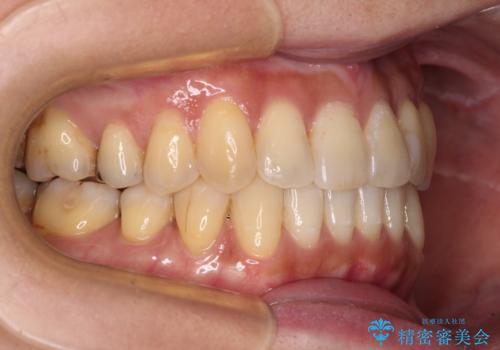

- 前歯のクロスバイトが気になり、インビザラインによる矯正治療を希望して来院された患者様です。

上顎側切歯(上の真ん中から2番目の歯)が舌側転位している場合、インビザラインでは仕上げきれないことが多く、更には無理して動かそうとすると歯髄壊死を起こすリスクが高いと言われています。

インビザラインで歯列を移動する前に、上顎前歯をワイヤー矯正で整え、その後上下歯列をインビザラインにて矯正治療を行うこととしました。

舌側転位している側切歯特有の、切縁の位置が不揃いであったり、根元が内側に引っ込んだ状態であったりという、インビザライン独特の仕上がりになることなく、きれいに整った歯列とすることができました。